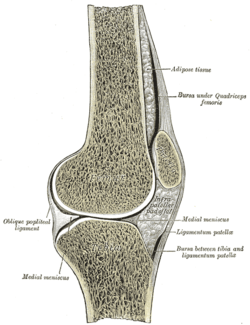

Sagittal section of right knee-joint. | |

- In the knee — the patella (within the quadriceps tendon). This is the largest sesamoid bone.[4]